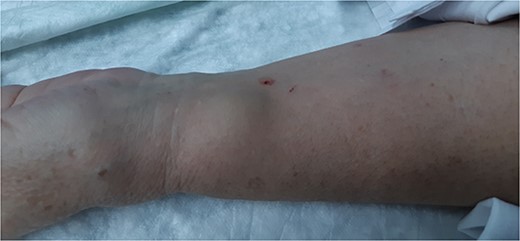

A 62-year-old female with a personal history of atrial fibrillation, hypertrophic cardiomyopathy, heart failure (Classes I–II/IV—New York Heart Association), arterial hypertension, dyslipidemia, Type II diabetes mellitus and smoking underwent two coronary angiography 6 months apart, both through left radial access with a 6Fr sheath and mechanical compression with PreludeSync. Punctures were performed by the Cardiology Department without an ultrasound and without any signs of difficulties in hemostasis. In the last procedure, the patient underwent coronary revascularization with stents and was medicated with dual antiplatelet therapy. The patient developed a pulsatile and expandable mass in the left wrist, 3 weeks after the last coronary angiography (Fig. 1). On physical examination, a painful, expandable and pulsatile mass with a murmur was identified. Complaints of paresthesia or signs of hand ischemia were not present. On duplex ultrasound, the mass had a longitudinal diameter of 2.2 cm, with a narrow neck and turbulent ‘yin-yang’ flow, compatible with a PA of the left radial artery. The patient underwent PA resection with arteriorrhaphy (longitudinal stitches), without any complications, and was discharged 24 h postoperatively (Figs 2 and 3). At 1-month follow-up, the patient was asymptomatic, presenting a palpable radial pulse and did not report any sensory deficits.